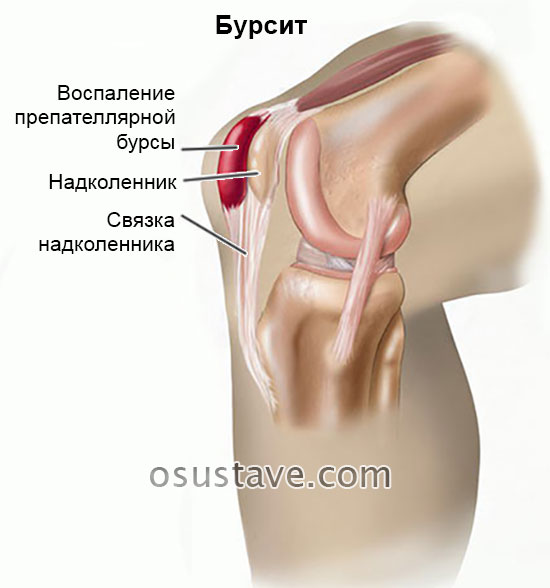

Заболевание сустава: симптомы и лечение